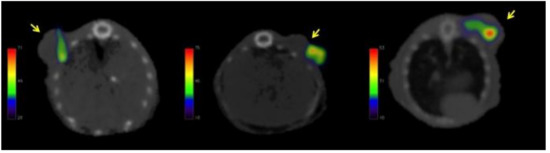

2.4. Biodistribution and Tumor Uptake in Mesothelioma Xenografts

| Time (h) | % Tumor | Tumor/Liver |

|---|---|---|

| 1 | 1.52 ± 0.15 | 6.61 ± 0.42 |

| 12 | 1.44 ± 0.23 | 6.21 ± 2.26 |

| 24 | 1.82 ± 0.18 | 8.46 ± 2.48 |

| 48 | 1.47 ± 0.31 | 5.71 ± 1.95 |